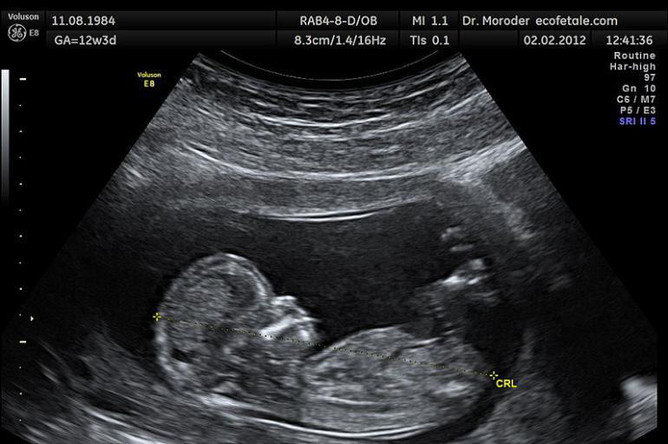

Эрдэмтэд: Агаарын бохирдлын улмаас жилд нэг сая ураг амьгүй төрж байна

Агаарын бохирдлын улмаас жилд нэг сая орчим ураг амьгүй төрдөг гэдгийг Хятад, Америкийн эрдэмтэд тогтоожээ. Энэ нь бүхий л төрөлтүүдийн тал хувь нь амьгүй төрөлт байх бөгөөд энэ нь агаарын бохирдолтой холбоотой гэсэн үг аж.

Эрдэмтэд бага болон дунд орлоготой 54 оронд 1998-2016 оны хооронд бүртгэгдсэн 45 мянган төрөлтийн мэдээллийг судалсан байна. Шаталтаас үүдэн агаарт хуримтлагддаг РМ2,5 бичил хэсгүүд жирэмсэн эхийн уушгиар дамжин, урагт хүрдэг бөгөөд амьгүй төрсөн ургийн уушги, элэг, тархинаас ийм хорт бичил хэсгүүд олддог байна. Ингэснээр эх урагт хүчилтөрөгч дамжуулахад саад болж, улмаар ураг амьгүй төрдөг байж болзошгүй гэсэн таамаглалыг эрдэмтэд дэвшүүлжээ.